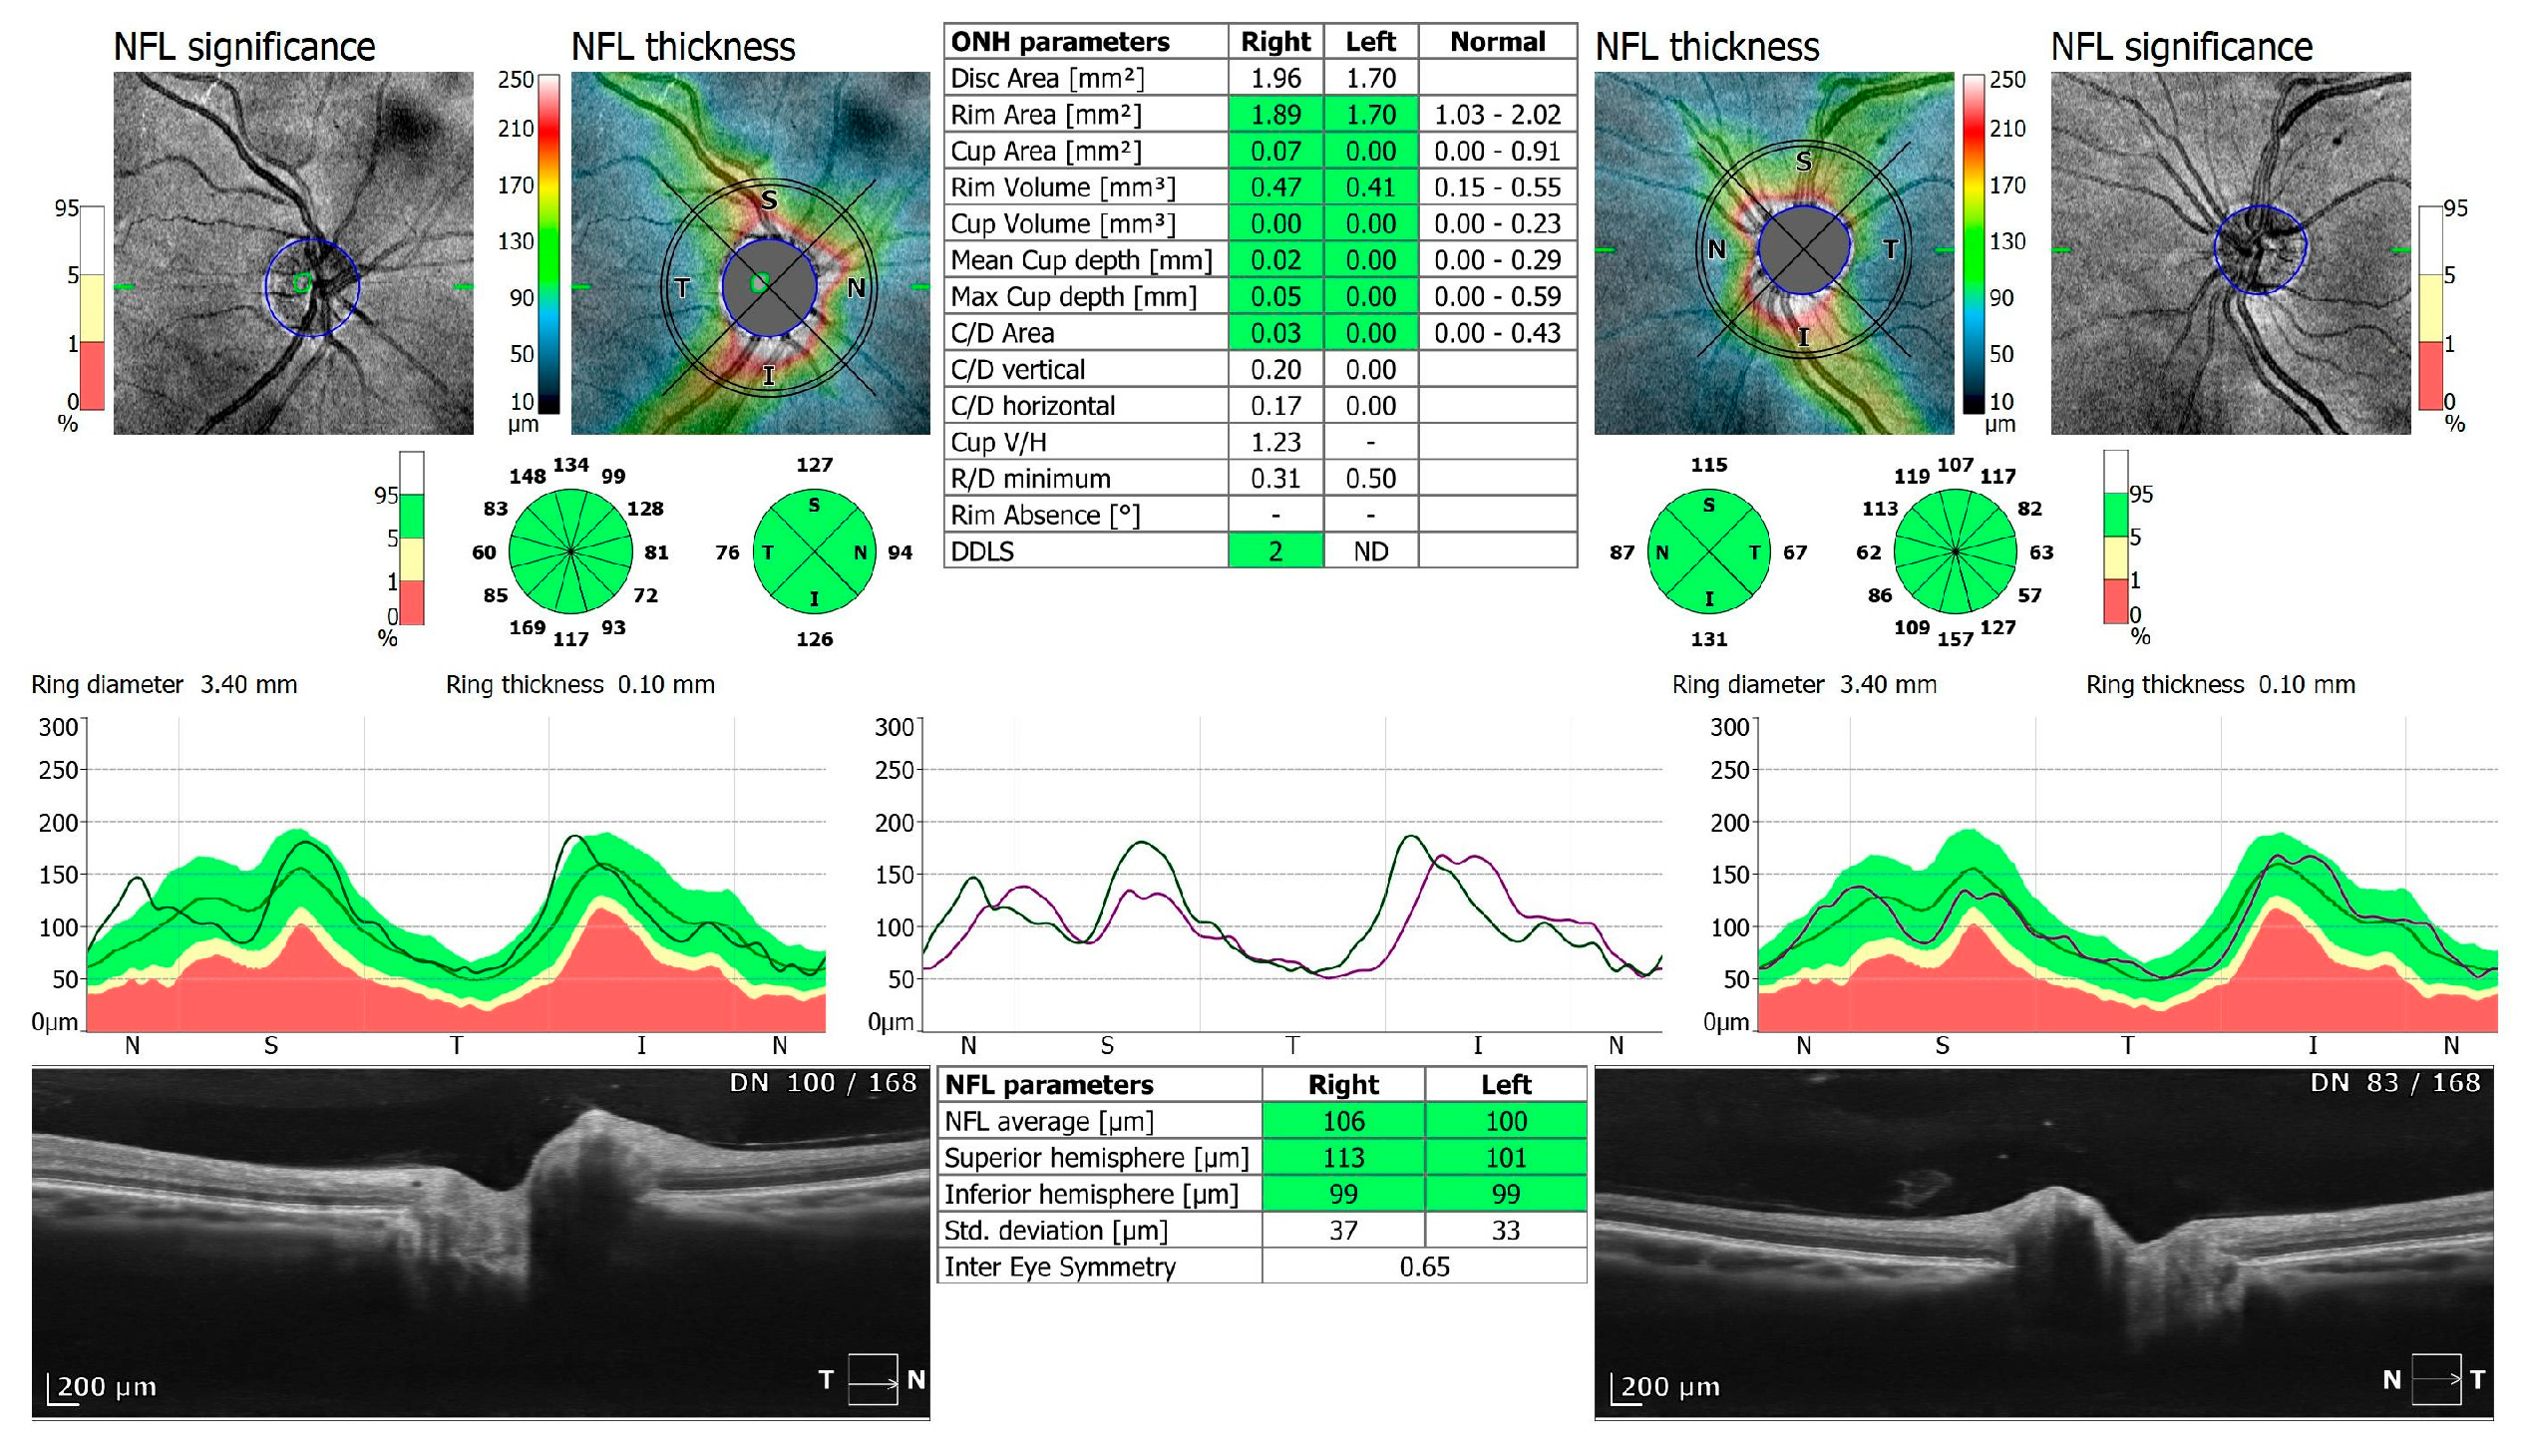

Figure 3.

OCT 3D disc scan 6 × 6 mm of COVID-19-positive patient. NFL, nerve fiber layer; ONH, optic nerve head.

Of the participants, 20 received oxygen therapy at flow rates ranging from 1–10 L, while 4 received high-flow intranasal oxygen therapy (HFNOT). Additionally, 5 patients were treated with Remdesivir therapy, 5 received COVID-19 convalescent plasma therapy, and 11 were treated with Tocilizumab. The demographics and clinical characteristics of the study participants are presented in Table 1. The mean time from a positive PCR test to study enrollment was 13.23 days, with a standard deviation of 8.18 days. The control group comprised 38 healthy individuals: 28 men and 10 women (control versus research group: p = 0.21), with an average age of 58 years, ranging from 33 to 69 years. All participants underwent two examinations, one upon admission and another upon cessation of therapy (6.70 ± 6.46 days). Spectral-domain optical coherence tomography (SD-OCT) was conducted using REVO FC 130 (Optopol Technology, Zawiercie, Poland). This device allows for high-resolution imaging and quantitative analysis of both the retina and cornea. The study specifically evaluated central retinal thickness, retinal nerve fiber layer (RNFL) thickness and optic disc parameters, alongside central corneal thickness and corneal epithelium thickness. The measurements were performed using built-in retinal and corneal layer segmentation tools provided by the OCT system, which automatically segmented the different layers of the retina and cornea to ensure precise and repeatable thickness measurements. OCT protocols included a 3D macula 7 × 7 mm scan, 3D disc 6 × 6 mm scan, and anterior radial 8 × 8 mm scan (Figure 1, Figure 2, Figure 3, Figure 4, Figure 5 and Figure 6). All patients had also undergone slit lamp examination, including indirect ophthalmoscopy.